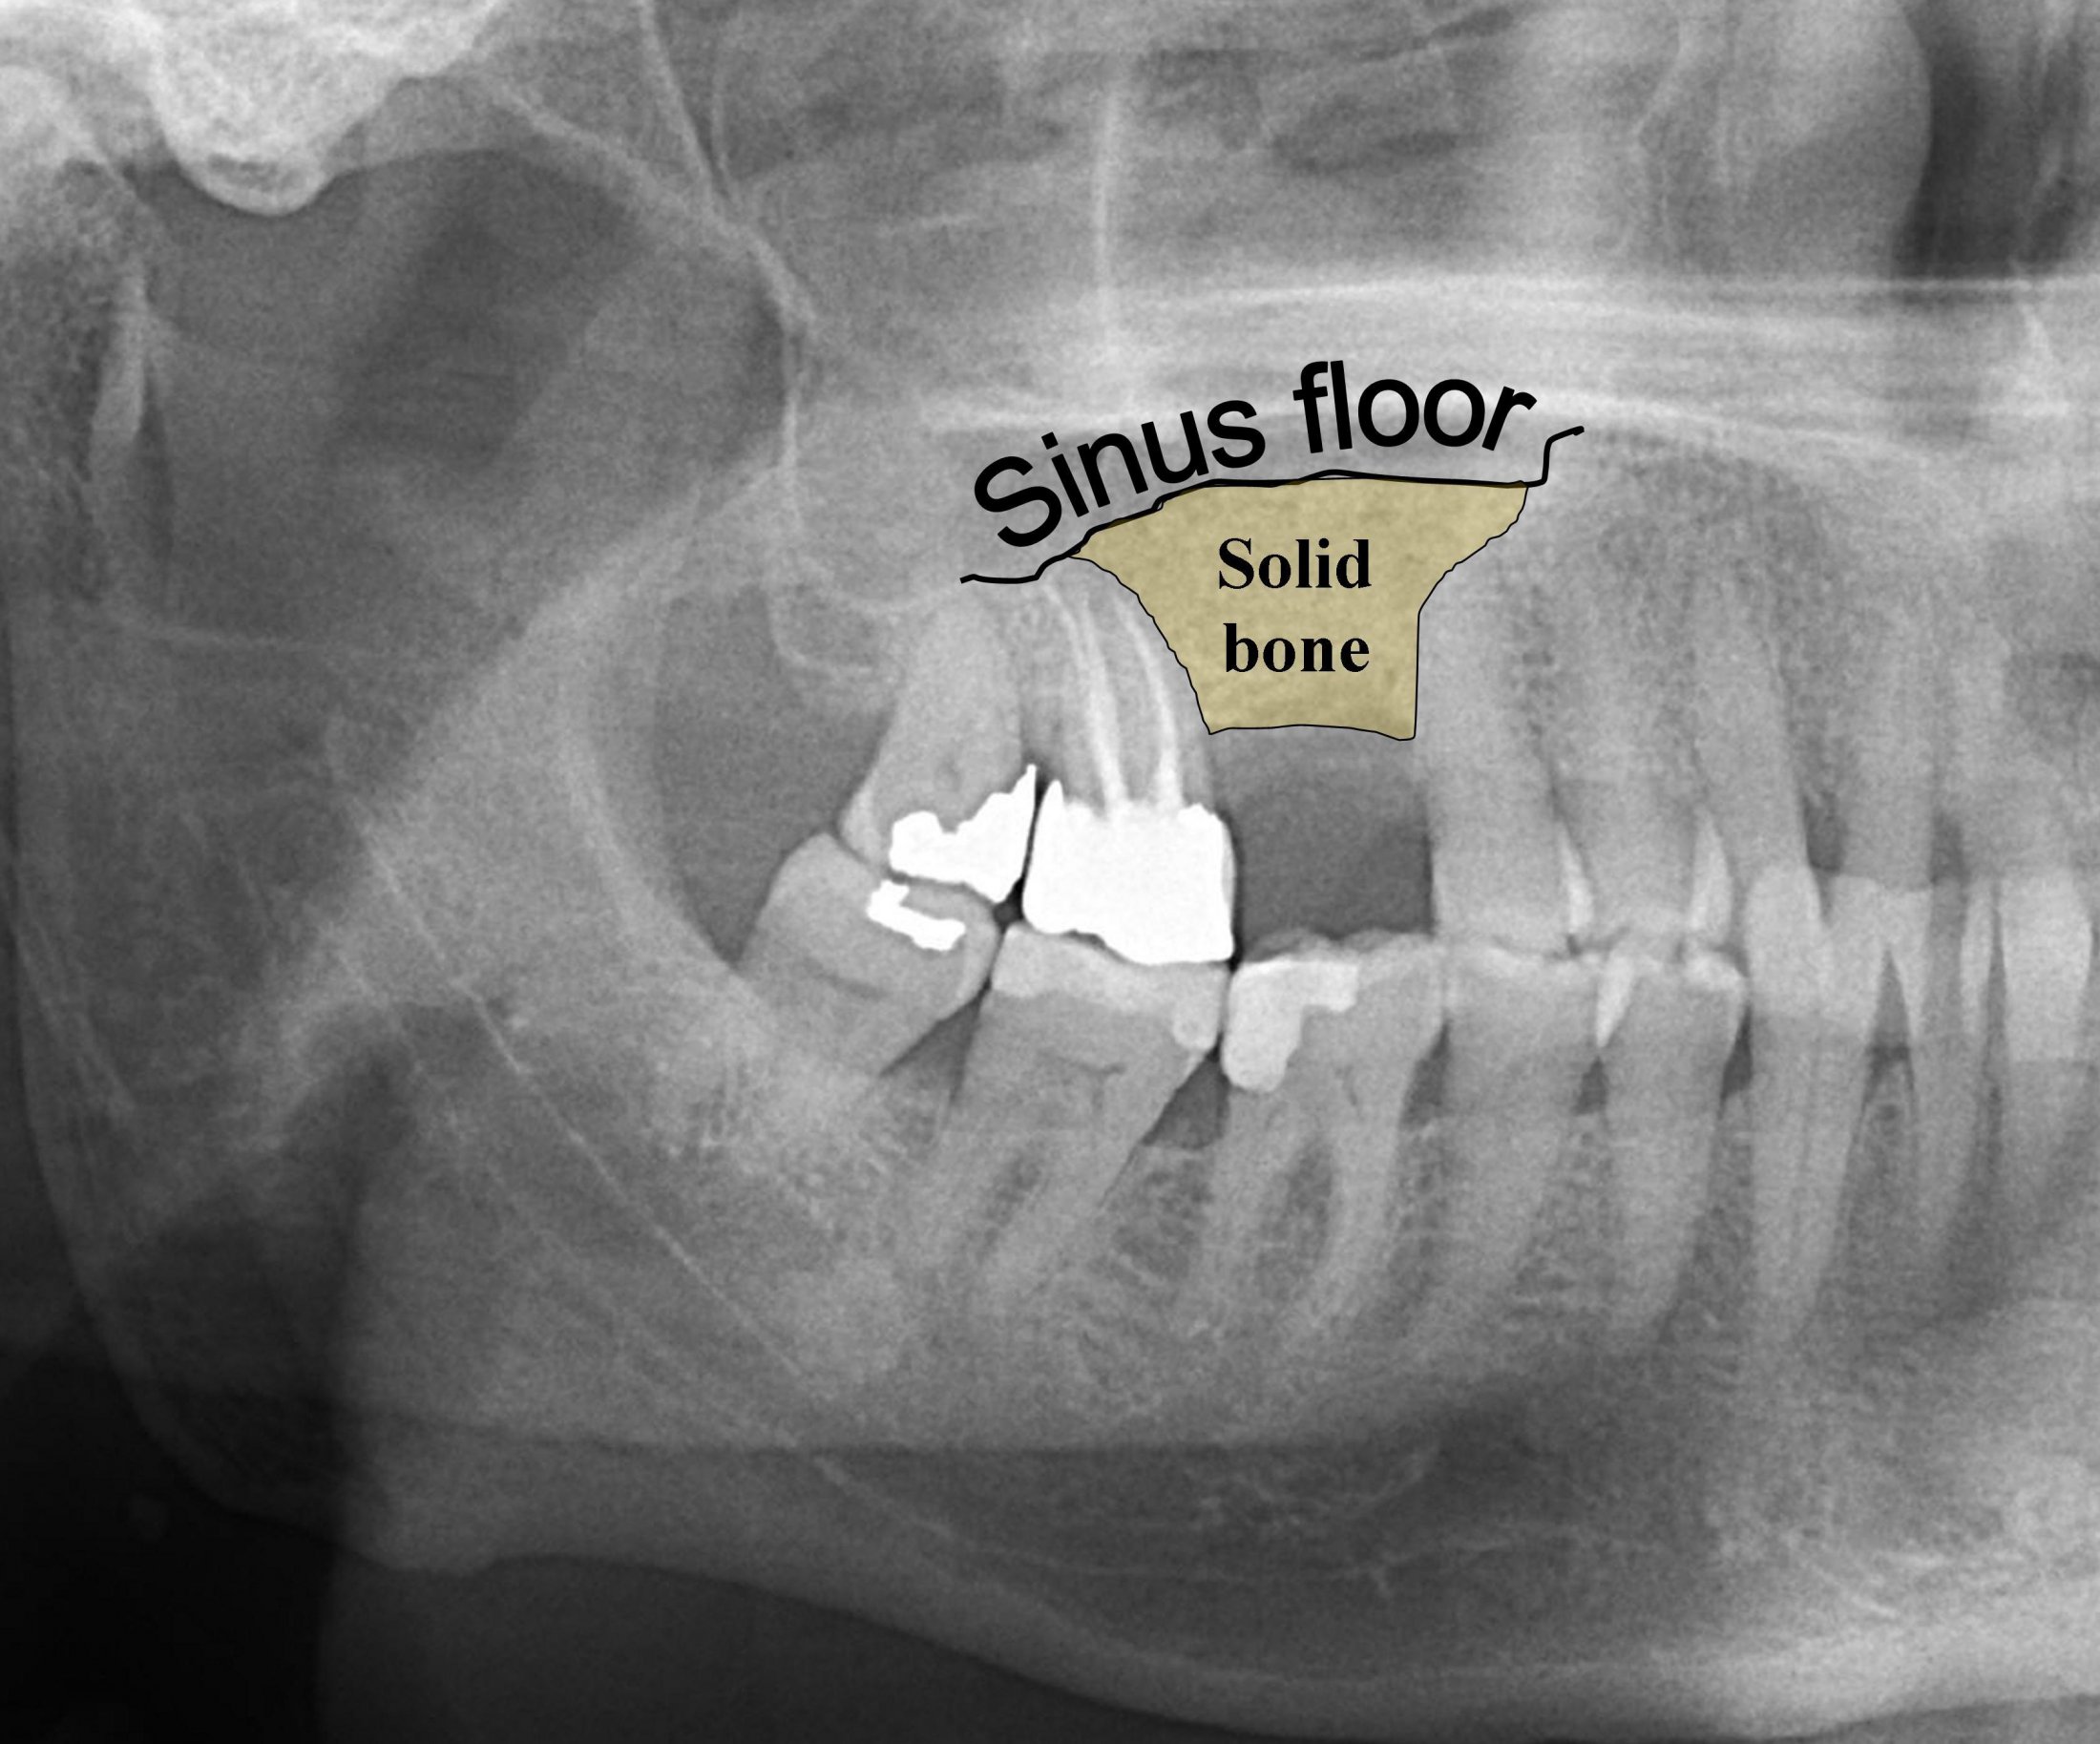

Dental X Ray Bone Loss . In addition, several other signs may alert your dentist to the possibility of osteoporosis: Reveal changes in the bone or in the root canal resulting from infection. This allows the surgeon to place. Reveal bone loss that accompanies gum disease. If you have significant bone loss, your dentist can use regenerative bone grafting to supplement the bone surrounding your teeth. The vertical bone defect is typically described by the tooth and surface where more bone loss is evident. Your dentist may assign a stage and a. Bone loss in the jaw and around teeth. If you note the bone between the mandibular second and third molar.